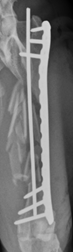

Cola underwent surgery the following day. The fracture was stabilised with an intramedullary pin (through the centre of the bone), and a bone plate & screws. The implants were placed through small incisions made at the top and bottom of the femur, leaving the central bone fragments undisturbed. Postoperative X-rays revealed restoration of the length and alignment of the femur.

Cola went home the following day with pain relief, and he was rested for six weeks. He had regular appointments with physiotherapist, Letty Piggott-Delves, to strengthen his leg and maintain range of motion after surgery. When Cola came for a recheck with Tim six weeks after surgery he was walking with no discomfort and a very mild lameness. X-rays showed early bone healing at the fracture site and over the two months Cola was returned to normal activity and has not looked back since!

Cola 4 Weeks Post-Op :